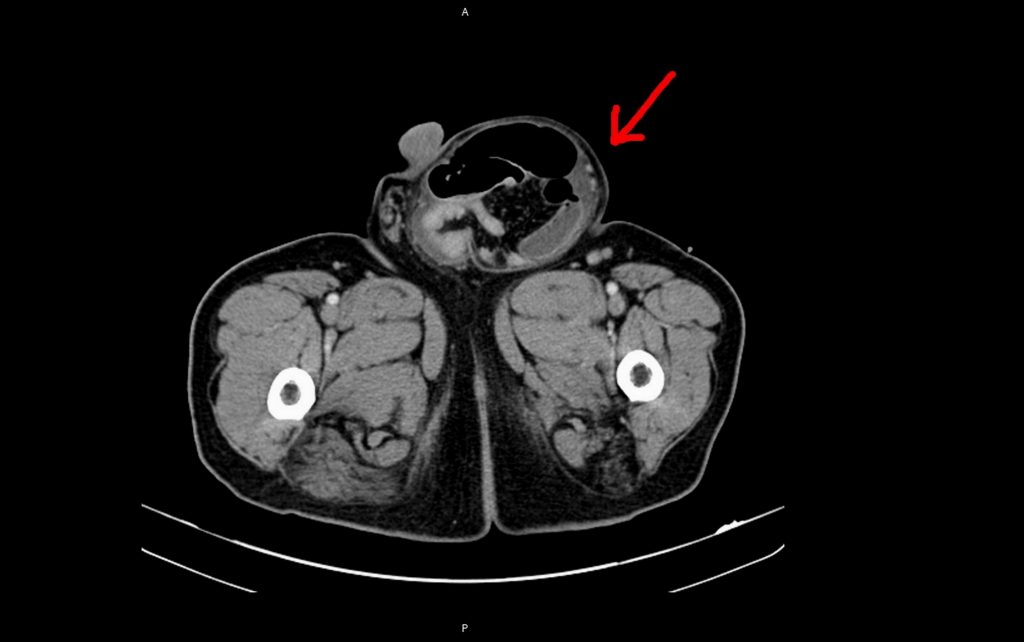

台北醫院外科醫師黃善鴻表示,透過電腦斷層檢查莊先生的「該邊」,發現其右側腹股溝腫塊直徑達15公分,小蘋果已變成大水梨了,需趕快手術處理,及術後恢復良好,且腎衰竭已自行改善,可免於終身洗腎,目前莊先生已順利出院。